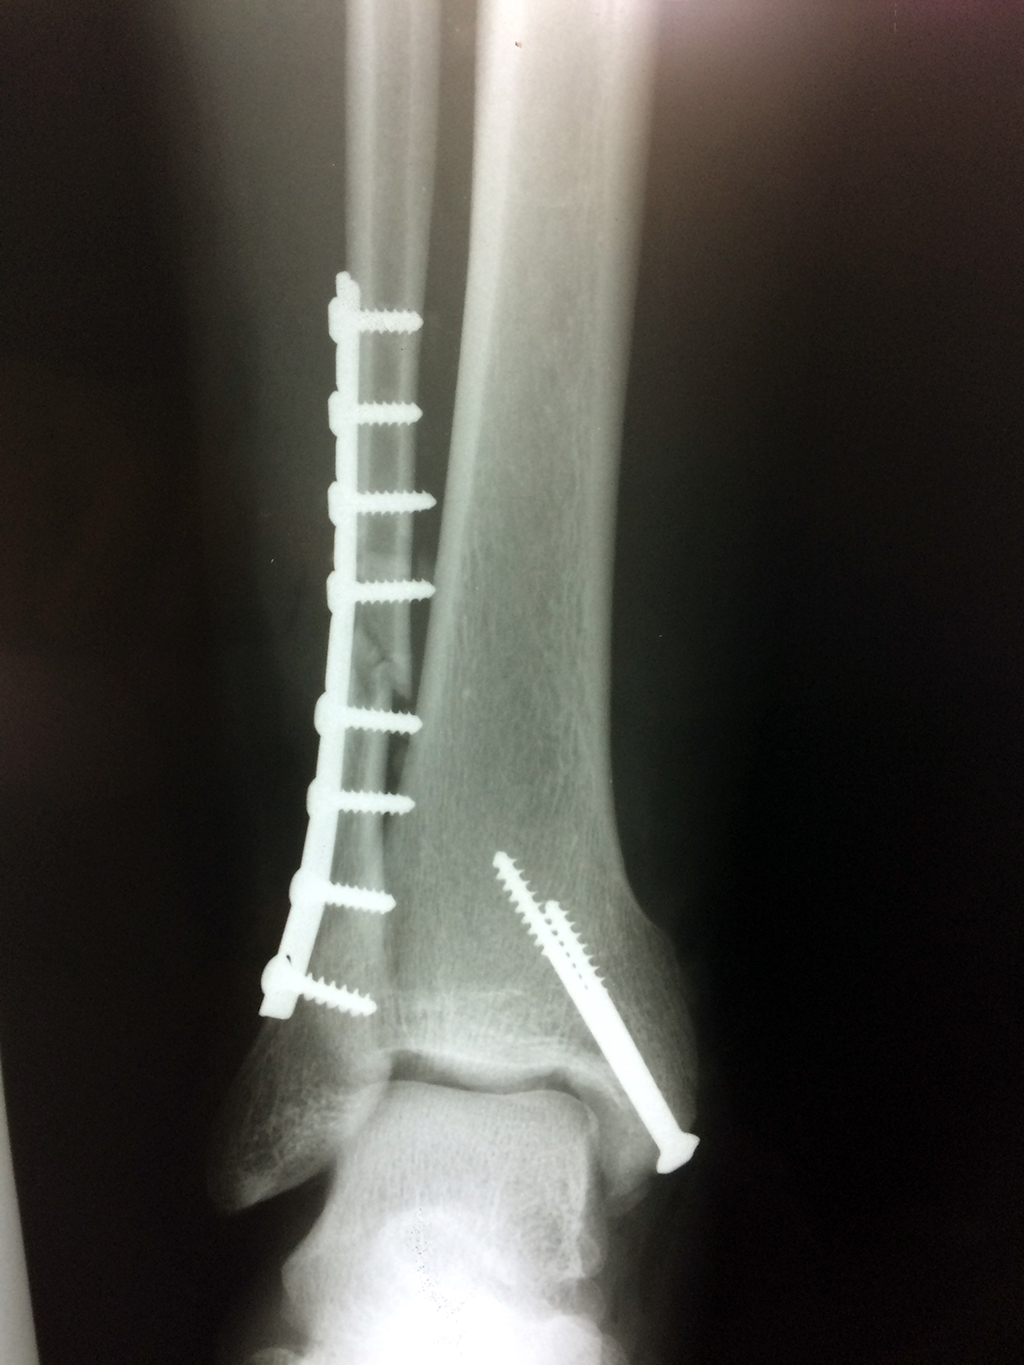

Cuando se necesita cirugía, es probable que esta implique el uso de clavijas de metal, tornillos o placas para sostener los huesos en su lugar mientras la fractura se consolida. Los elementos de soporte pueden ser temporales o permanentes.

Algunas fracturas de tobillo pueden requerir cirugía si:

- Los extremos de los huesos están desalineados entre sí (desplazados).

- El médico cree que sus huesos probablemente no sanen apropiadamente sin cirugía.

- El médico considera que la cirugía puede permitirle una recuperación más rápida y confiable.